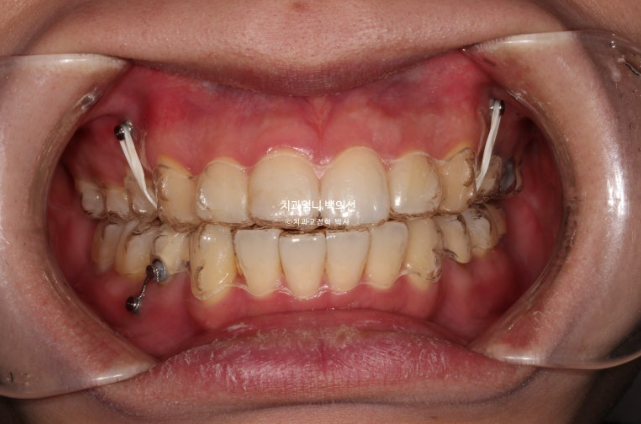

치료시작 9개월째 발치공간이 1/3가량 줄어든 모습입니다.

장치 협조도가 좋은 환자분이었습니다.

치료 도중 앞니 교합 깊어짐이 보여 앞니에 교정용 나사인 미니스크류를 심고 고무줄을 걸면서 앞니 수직적 컨트롤을 도모합니다.

이렇게 원래 치료계획에는 없던 부분이지만 치료 중간 모니터링 후 추가장치나 고무줄이 필요한 경우가 있습니다.